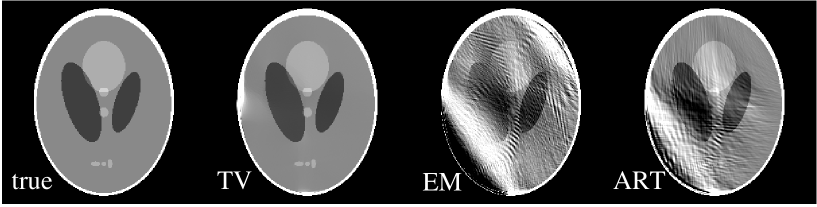

We explore further reduction in the scanning angle by taking 64 angular samples uniformly distributed over an angular range of only 90∘, covering the first quadrant of the Shepp-Logan phantom in Fig. 7. We display in row one of Fig. 7 images reconstructed by use of the TV, EM, and ART algorithms. The number of iterations for the TV, EM, and ART reconstructions is 10,000. In this case, there were 26,420 non-zero projection measurements, which would seem to be sufficient for the TV algorithm considering the sparseness of the phantom’s image gradient. But the instability of the corresponding linear system appears to be too strong for accurate image reconstruction as can be seen in the reconstructions shown in the upper row of Fig. 7. In the middle row of Fig. 7, we show the profiles along central lines in the horizontal and vertical directions of the TV image. The corresponding true profiles are also displayed as the thin lines. The TV image contains a deviation from the true phantom on the left-hand edge, which is evident in the shown horizontal profile. On the other hand, the EM and ART reconstructions are highly distorted. We have studied in row three of Fig. 7 the profiles along central lines in the horizontal and vertical directions of the EM and ART images. Distortions in these images are clearly shown in these profile plots. We have also studied the image error as a function of iteration number in an effort to determine whether or not the TV algorithm will converge to the true image. For the previous cases the image error was tending to zero, but for this 90∘ scan the image error appears to converge to a small but finite positive number. The system matrix corresponding to the 90∘ scan appears to violate somewhat the ERP.